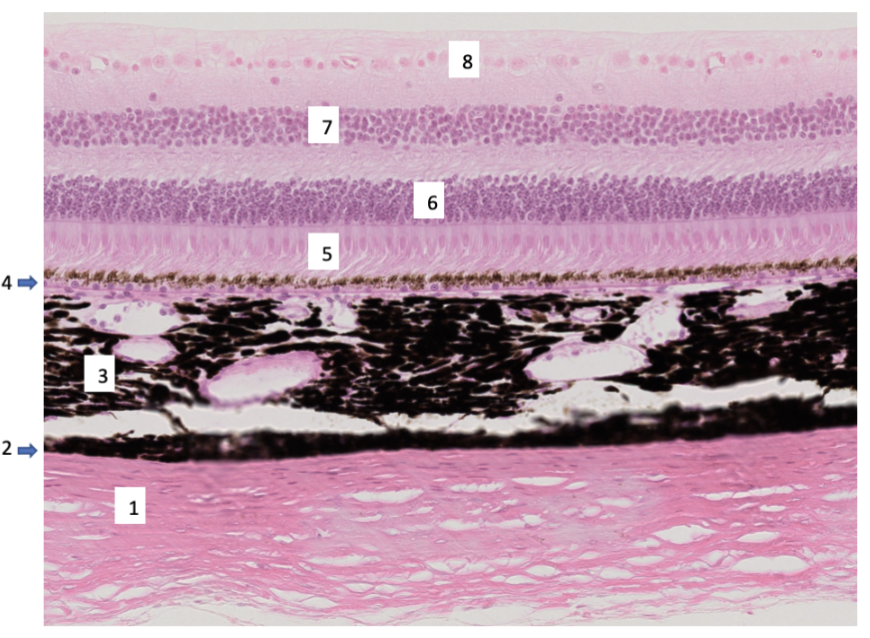

Bilden visar en del bakre ögongloben. Svara på frågorna genom att ange rätt siffra. (0,5p per rätt svar, totalt 2p)

a) Vilken siffra markerar det lager som är kontinuerlig med hornhinnan (cornea) om man följer det anteriort (framover)?

b) Vilken siffra markerar lagret där de bipolära neuronen har sin cellkärna?

c) Vilken siffra markerar den ljuskänsliga delen av retina (som registrerar ljus)?

d) Vilken siffra markerar celler vars axon bildar synnerven?